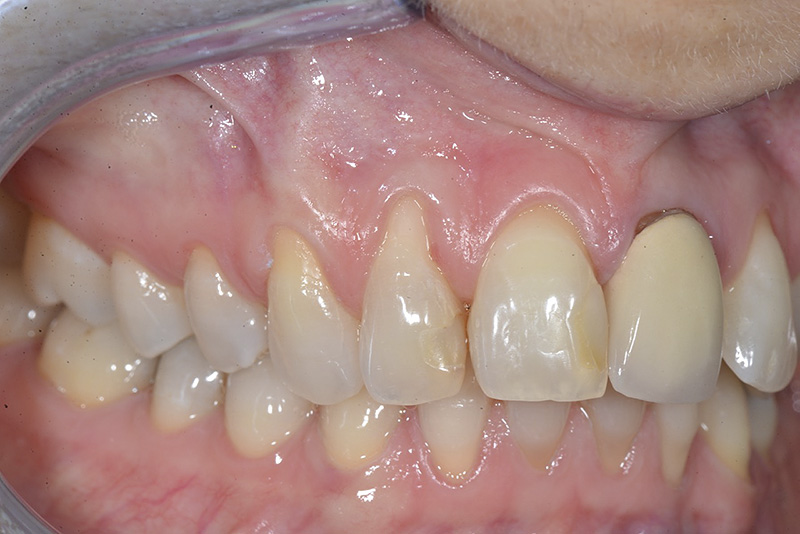

PREMESSA: in seguito all’estrazione dell’incisivo laterale superiore di destra, resasi necessaria per cause batteriche, si decide di affrontare il caso con il posizionamento di un impianto in sostituzione dell’elemento mancante dopo guarigione del sito infetto. Con tecniche rigenerative sia dei tessuti ossei mancanti a causa dell’infezione pregressa, sia dei tessuti gengivali che appaiono inizialmente troppo spostati in alto, si ripristina una corretta morfologia delle parabole (contorni) gengivali e delle papille interdentali (triangoli di gengiva tra due denti vicini).

Vengono utilizzati 2 tipi di provvisori: il primo, cementato ai denti vicini, viene utilizzato dal momento dell’estrazione del dente fino ad impianto osteointegrato (circa 6 mesi); il secondo, avvitato direttamente all’impianto, ha una funzione di prova estetica ma soprattutto di guida per la maturazione dei tessuti gengivali peri-implantari portandoli verso la maturazione completa prima di posizionare la corona finale in disilicato di litio.